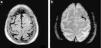

Por su parte, en el segundo grupo (PRES) se genera un desbalance en el manejo de la tensión arterial entre la circulación anterior y posterior durante los cuadros de hipertensión. Su presentación típica se basa en áreas de edema vasogénico en las zonas correspondientes a la circulación posterior, que habitualmente resuelven con la normalización de la tensión (fig. 8). Sin embargo, existen formas atípicas en las que el daño puede ser irreversible y otras en las que las lesiones exceden el territorio vascular habitual.

Cefalea durante crisis hipertensiva. (a) La TC en corte axial registra áreas hipodensas en la sustancia blanca posterior con una distribución bilateral. (b) En la secuencia en ponderación T2, corte axial, se observa la alteración de señal en dicha sustancia, mientras que (c) en la RM de control, después de la resolución, se identifican hallazgos vinculables a una encefalopatía posterior reversible.